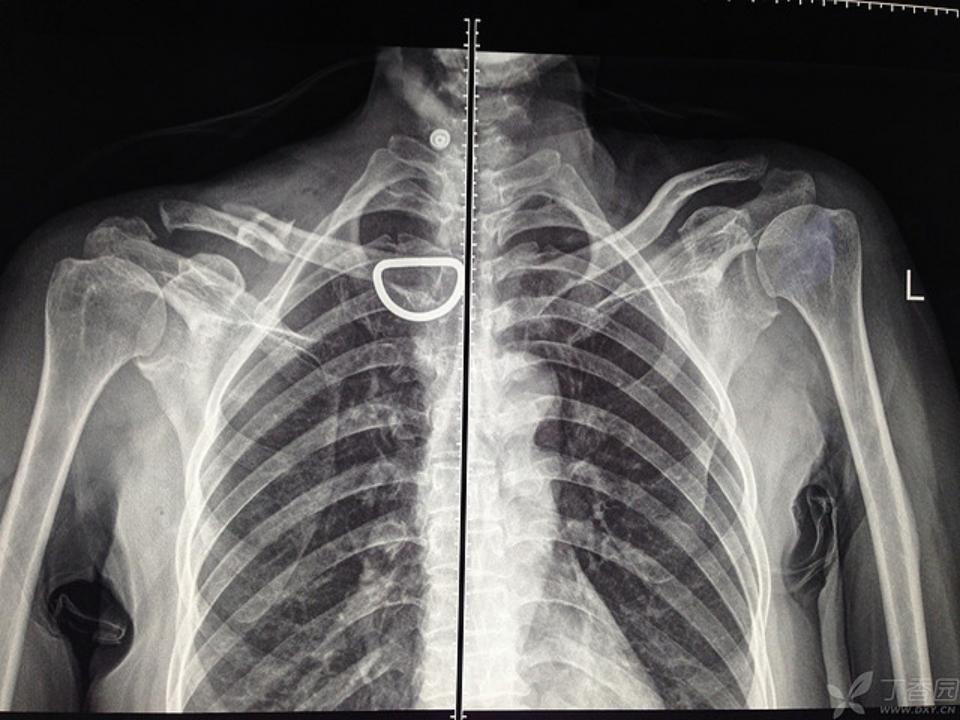

还有取出器械与螺钉不配套导致手术时长达 6 小时的;还有螺钉滑丝的;还有患者将片子遗留家中,我要值班医生翻拍电脑上的片子,由于图像模糊导致一个垫片差点遗漏未取出,最后幸亏透视躲过一劫。

上面就是值班医生发给我的片子,大家找找那个差点遗漏的垫片在哪里?